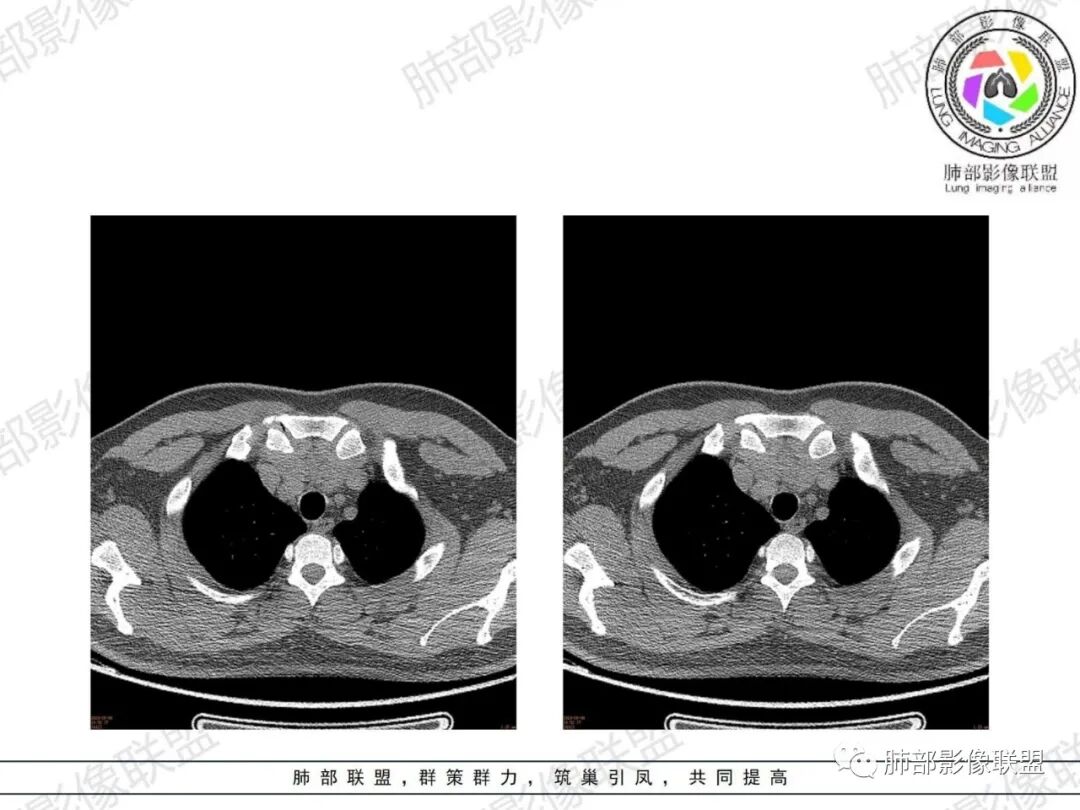

凝睦:有肌无力症状,定位胸腺来源,肿块形态较弥漫,边界清,密度低,考虑胸腺瘤或胸腺增生。

飞鹰行动:青年人,前上纵膈占位性病变,病灶与局部周围组织分界不清晰(有侵袭性),密度稍低于正常血管(无纵膈窗),没有可见钙化,脂肪密度。无增强,这个年龄,这个部位肿块,常规考虑生殖类肿瘤,淋巴瘤和胸腺增生待排除。

简·爱:年轻男性,26岁,小于30岁 (黄勇老师说小于30岁,诊断胸腺瘤要慎重),双下肢无力一个月,亚急性病程,前纵隔胸腺区不规则软组织密度灶,密度较均匀,无明显钙化和坏死、出血,隐约见条状低密度分隔影和斑点装脂肪密度,病灶比较软,浅分叶,胸腺轮廓基本还在,不知道强化怎么样,考虑胸腺增生,鉴别,胸腺瘤瘤,淋巴瘤,生殖细胞瘤。

King:确实在影像不足的情况下,年龄和症状是重要考量因素。影像形态膨胀不足,钻隙明显,密度似夹脂肪,首先胸腺增生,其次淋巴瘤,胸腺瘤或癌不首先考虑了。

毛勤香:青年男性,26岁,肌无力,病灶贴着主动脉,有结节感,感觉含脂,首先考虑胸腺增生,鉴别胸腺瘤,淋巴瘤,生殖来源肿瘤,得看一下重建和增强。

傅昌瑜:青年男性,双下肢乏力1月。前纵隔肿块,好像多结节堆积,包绕纵膈血管,脂肪间隙清晰,密度均匀。前纵隔占位常见疾病谱有:胸腺瘤、胸腺癌、胸腺增生、淋巴瘤、生殖细胞瘤、畸胎瘤。没有多密度成分,首先排除畸胎瘤;26岁病例基本排除胸腺癌,诊断胸腺瘤亦需慎重。首先考虑淋巴瘤,鉴别胸腺增生、生殖细胞肿瘤。

弹指之间:青年男性,双下肢无力,前纵隔肿块,形态不规则、分叶征,无钙化,无增强图像,考虑1.胸腺增生(年纪这么轻不考虑胸腺瘤),2.淋巴瘤(形态看符合、但密度似乎不均匀);3.生殖细胞类肿瘤(形态不呈球形)。综合:胸腺增生>淋巴瘤。

郑氏刀刀:年纪这么轻,边缘膨隆感局部较弱,质地软,中央有脂肪浸润样密度,伴肌无力,常规考虑胸腺增生,鉴别淋巴瘤(密度较高,均匀),胸腺瘤(密度较高,无脂肪浸润,质地较硬),精原细胞瘤(类似淋巴瘤,可坏死)。

被强煎的蛋.¢?:青年男性,胸骨后前纵隔内胸腺增大,厚度增加,边缘光整膨胀力弱,分叶浅,与胸骨及主动脉弓和心前缘接触面较宽,与周围正常结构分界清楚,无淋巴结肿大及胸膜、心包受累等。拟考虑胸腺增生。